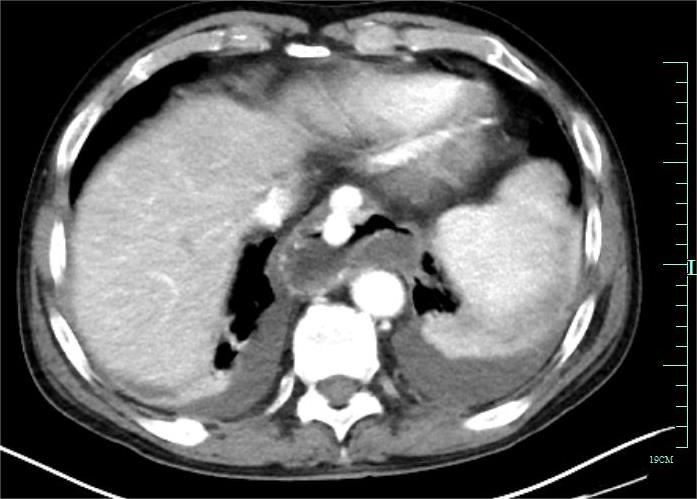

• 超声内镜引导下胃旁曲张静脉精准断流术治疗食管胃静脉曲张出血的疗效分析(附20例报告)

2025, 31(8):85-90. DOI: 10.12235/E20250036

摘要 (153) HTML (42) PDF 5.38 M (98) 评论 (0) 收藏

摘要:目的 探讨超声内镜引导下胃旁曲张静脉精准断流术治疗食管胃静脉曲张出血的疗效。方法 回顾性分析2024年1月1日-2024年12月31日于该院接受超声内镜引导下胃旁曲张静脉精准断流术治疗的20例肝硬化食管胃静脉曲张出血患者的临床资料,并评估治疗效果。结果 20例患者均顺利完成超声内镜引导下胃旁曲张静脉精准断流术;注射组织胶联合置入弹簧圈(16例)和单独注射组织胶(4例)均成功阻断胃旁来源的曲张静脉;所有患者均未发生穿孔、食管贲门狭窄、大出血、败血症和异位栓塞。1例单独注射组织胶的患者,术后胃旁曲张静脉少许渗血,经降低门静脉压力治疗3 d后好转,另1例单独注射组织胶患者,术后出现低热,抗感染3 d后体温恢复正常。结论 超声内镜引导下胃旁曲张静脉精准断流术治疗食管胃静脉曲张出血的临床疗效好,异位栓塞、大出血、感染和穿孔等并发症少,但仍需要密切随访,观察胃旁曲张静脉的排胶问题。